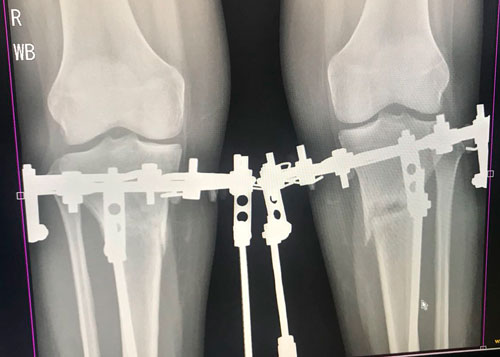

Исходник 33 года.

Дата операции 26.04.2018г.

Перед крутками